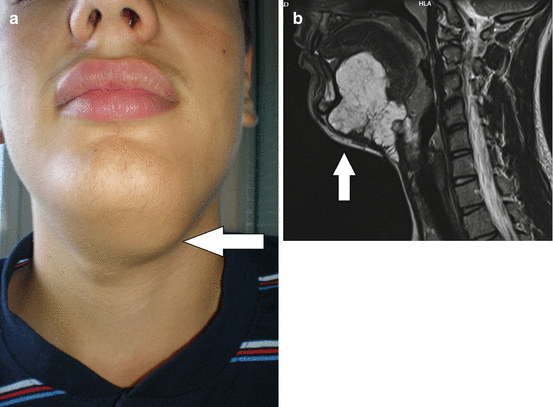

Fig. 15.3

Venous malformation of the sublingual region: (a) submandibular leasion; (b) magnetic resonance imaging of the lesion

The most common types of VMs are sporadic VM, glomuvenous malformation (GVM), and blue rubber bleb nevus (BRBN) syndrome [1, 4–6]. Most VMs occur as sporadic and solitary (approximately 94% of VM) (Fig. 15.2) [1, 2, 4, 7, 14]. Sporadic VM is usually greater than 5 cm, single, and mostly located on the head and neck and extremities (Fig. 15.3a, b) [2, 8, 13].